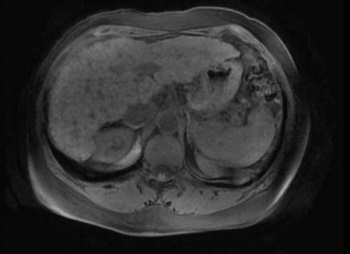

Annak ellenére, hogy jelentős eredményeket modern hepatológiai megfigyelt növekedését különböző sérülések és az epevezeték és a fogékonyság a krónikus és a hosszú távú, elhúzódó persze, így gyors diagnózis egyre prioritást élvez. Amellett, hogy a felmérés, anamnézis és a laboratóriumi vizsgálatok, a legtöbb információt, amely lehet tekinteni, mint a vérkép, melyik az a funkcionális állapotát az alábbi módszerek segítségével a tanulmány az epe rendszer.

Az ultrahangvizsgálat a epe rendszer

Képzés, amely szükséges a magatartás e tanulmány meglehetősen egyszerű, de szükséges, hogy minél teljesebb képet. Ennek célja, hogy maximalizálja a csökkentés a gázképződés a belekben a bél hurok nem zárja felülvizsgálatát a vizsgált szervekben. Ehhez előestéjén a felmérés szükségességét, hogy végezzen egy tisztító beöntés vagy egy hashajtó. Ez az eljárás a leghatékonyabb, három nappal az esemény előtt meg kell ragaszkodni a diéta, amely csökkenti az elgázosítás folyamata. Meg kell végezni éhgyomorra, mivel az utolsó étkezés kell legalább 8 órán át.